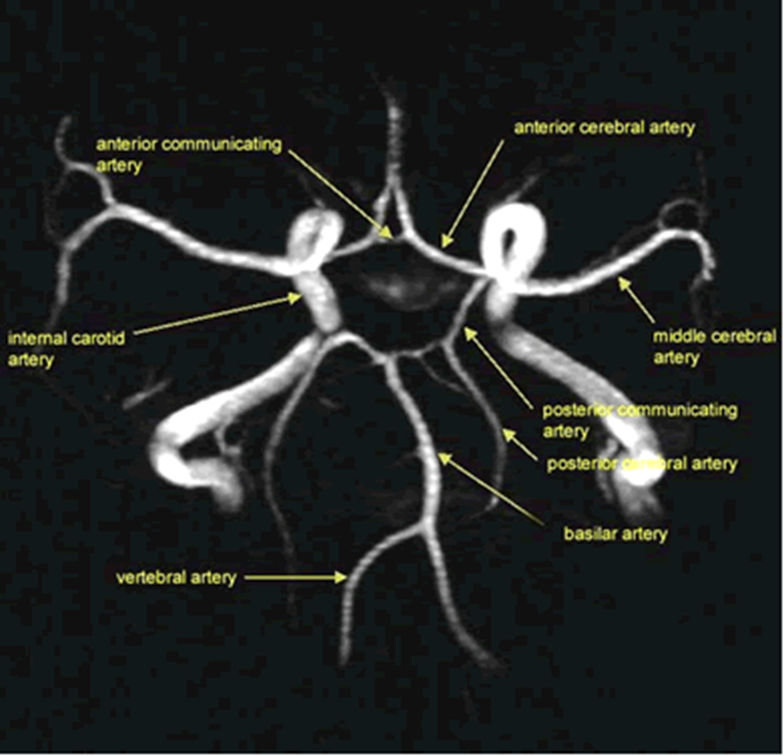

how is blood supplied to the brain

•The brain is supplied by two pairs of arteries that arise from branches of the aortic arch:

The internal carotid arteries (80%) ascend in the anterior part of the neck, arising from the bifurcation of the common carotid arteries.

The vertebral arteries (20%) arise from the subclavian arteries and ascend in the lateral cervical region, passing through foramina in the transverse processes of the upper six cervical vertebrae.

•The arteries at the base of the brain are linked by communicating vessels to form the circle of Willis (COW).

•This gives rise to anterior, middle and posterior cerebral arteries on each side, which supply most of the cerebral hemisphere.

•The cerebral blood supply can be divided into anterior and posterior circulations

what is the circle of willis

•Formed by a single anterior communicating vessel and two

posterior communicating vessels.

what is anterior circulation

•The internal carotid artery divides at the base of the brain, giving rise to the middle cerebral artery (MCA) and the anterior cerebral artery (ACA).

•The MCA is the larger of the two and receives 80% of the internal carotid blood flow. For this reason, cardiogenic emboli are much more likely to enter the MCA than the ACA.

•The MCA continues laterally between the frontal and temporal lobes and emerges from the lateral sulcus to supply most of the hemispheric convexity.

•The ACA passes forward and medially to meet its partner between the cerebral hemispheres.

what is posterior circulation

•The posterior circulation supplies the remainder of the cerebral hemisphere and the posterior fossa contents (brain stem and cerebellum).

•The two vertebral arteries unite in front of the brain stem to become the basilar artery, which splits into the two posterior cerebral arteries (PCA).

•These vessels pass posteriorly, above the tentorium cerebelli, to supply the occipital lobe and the inferior surface of the temporal lobe.